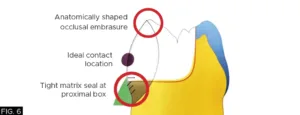

Proper use of a sectional matrix system (e.g. DualForce™ Sectional Matrix System, Clinician’s Choice®) ensures tight and anatomically correct proximal contacts. Proximal and occlusal embrasures should allow for self-cleansing by the tongue and gingival embrasures that are anatomically shaped to prevent food impaction and periodontal irritation.

A 4.5 mm DualForce™ Ultra-Wrap™ Sectional Matrix Band (Clinician’s Choice) was chosen and inserted on the distal side of tooth #28 (#44) and the band was sealed along the gingival margin with a #4 DualForce™ Active-Wedge™ (Clinician’s Choice). The matrix band was then secured in place with a pre-molar DualForce Matrix Ring (Clinician’s Choice) adapting the sectional matrix band to the tooth and providing the separation force necessary for a tight contact. (FIG. 5)

DualForce Ultra-Wrap Matrix Band, Active Wedge, and Molar Ring were placed allowing for proper adaptation and provide necessary separation force.

The DualForce Ultra-Wrap matrix band also creates the proper proximal tooth anatomy as well as the proper occlusal embrasure anatomy, while the Active-Wedge seals the proximal box.

(FIG. 6, 7)